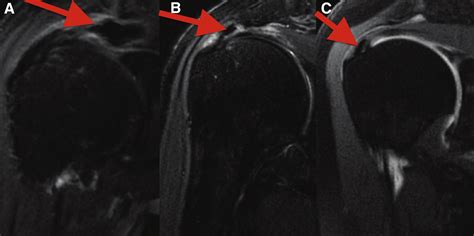

MRI Usually not needed for diagnosis but may be used to rule out other structural issues like tears.